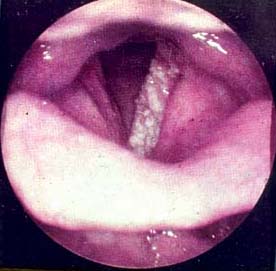

正常聲帶喉癌2.聲門上癌 生長於喉室、室帶、會厭,也包括杓狀軟骨及杓會厭皺襞的腫瘤。

顯微喉鏡

顯微喉鏡所見2、喉結核 喉結核的患者有不同程度的喉痛,肺部大多有結核病灶共存。病變呈顆粒狀,粉紅色或蒼白水腫,常伴有淺潰瘍,覆蓋膿性分泌物,後聯合為喉結核的好發部位,而喉癌者罕見。進行抗癆治療有效,活檢細胞學檢查和分泌物塗片,找抗酸桿菌對確診有幫助。

喉白斑 3、喉角化症及喉白斑 其表現為音啞喉內不適,中年以上男性多發,喉鏡見聲帶增厚,呈粉紅色或白色斑塊,周圍組織常有炎性反應,多為單側,亦可累及雙側聲帶,容易復發,有惡變傾向。病理活檢可確診。